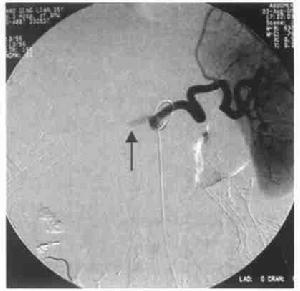

肝移植術2.2出血患者一般情況出血患者共10例,發病率11.5%(10/87);死亡4例,病死率40%(4/10)。基礎疾病分別為慢性B肝肝硬化合併肝癌(5例),慢性肝炎肝硬化合併肝性腦病(2例),慢性重型肝炎(2例),慢性肝炎肝硬化合併門脈高壓、脾功能亢進(1例)。其中採取保守治療5例,5例患者經保守治療後出血得到控制,其中1例治癒無併發症、4例並發MODS死亡,其中加用重組活化凝血因子Ⅶ者3例(其中1例出現肝動脈血栓);採取手術患者5例,其中用重組活化凝血因子Ⅶ者無效後手術者2例,手術時發現出血部位分別為膽管動脈吻合口處小動脈(2例)、手術區肝膽外的小動脈(2例)、肝動脈吻合口處小滋養動脈(1例),均治癒無其他併發症出現。

3.2手術因素包括未止血的痙攣血管解痙後出血,縫扎線松解、脫落後出血,供肝包膜血管及腹壁等血管未妥善止血,徹底止血後血栓脫落等,這種出血多為動脈性出血,一般靠補充血小板、凝血因子及凝血酶原等不能糾正,手術探察多可發現出血血管,需再手術治療。本研究中5例患者經補充血小板、凝血酶原等後不能糾正,而行剖腹探查術,而手術止血後徹底止血則屬此類,且手術中證實出血部位均為動脈,分別為膽管動脈吻合口處小動脈2例、手術區肝膽外的小動脈2例、肝動脈吻合口處小滋養動脈1例。

肝硬化失代償患者,尤其是高MELD評分患者,術前凝血功能極差,臨床上一般給予積極糾正後再行手術治療,但即使是術前凝血功能正常的患者行肝部手術仍存在大出血的風險[4]。而重組活化凝血因子Ⅶ的使用使嚴重肝病合併凝血功能障礙的患者行外科手術(包括肝移植術)成為可能,同時重組活化凝血因子Ⅶ的使用也可減少肝移植患者手術中出血和輸血量[5],但是仍存在手術後出現肝動脈栓塞的風險[6],而重組活化凝血因子Ⅶ在肝移植術後可以減輕腦出血損害,但是手術後使用重組活化凝血因子Ⅶ者國內罕見報導,而本研究中肝移植術後腹腔出血使用重組活化凝血因子Ⅶ5例中,其中1例出現肝動脈栓塞,可見肝移植術後使用重組活化凝血因子Ⅶ有出現肝動脈栓塞的風險。